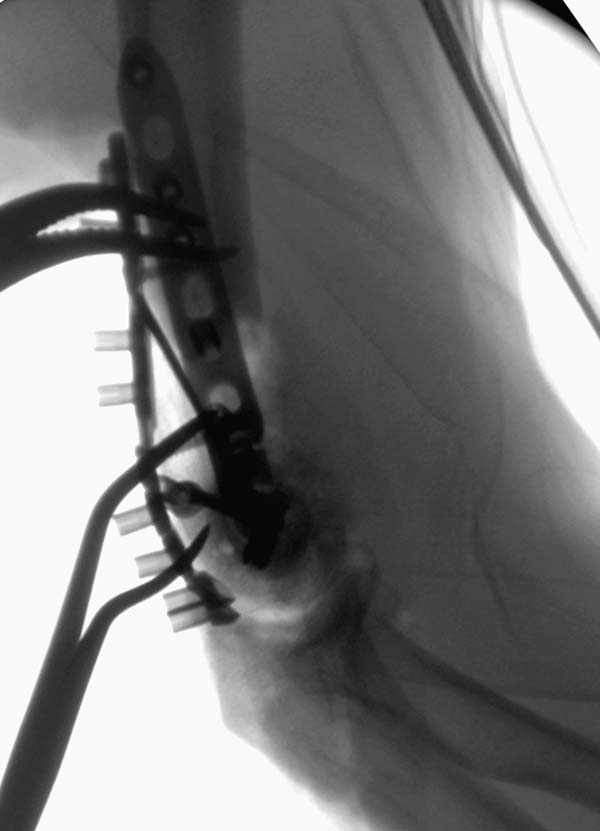

Примеры: первому более 15 лет фиксирован шурупом и tension band

technique, а второй перелом открытый больной 80 лет, после наружного

фиксатора в первом этапе и окончательная фиксация вторично. Третьий раз

внесуставная остеотомия...